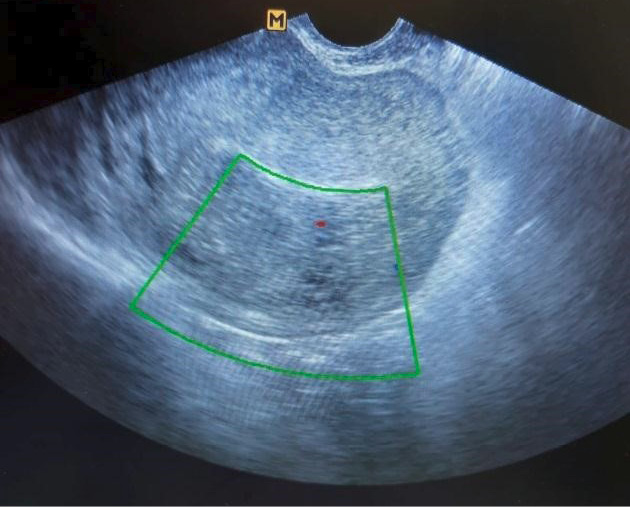

При УЗИ органов малого таза (рис. 1) тело матки размерами 82,7×67,8×85,1 мм. М-эхо 11 мм, неоднородной структуры. Обращало на себя внимание наличие множественных трубчатых анэхогенных структур по задней стенке матки, расположенных от эндометрия до серозного слоя, в режиме ЦДК регистрировали кровоток. Данная картина более характерна для АВМ матки. Правый яичник расположен типично, размерами 30,2×25×23,6 мм, с единичными фолликулами диаметром 3–5 мм. Левый яичник также расположен типично, размерами 31,2×24,5×24,1 мм, с единичными фолликулами диаметром 3–4 мм. Заключение: УЗ-картина может соответствовать АВМ матки.

Рис. 1. Ультразвуковая картина артериовенозной мальформации матки.

Fig. 1. Ultrasound picture of arteriovenous malformation of the uterus.